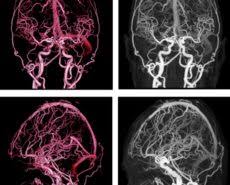

Van Da Beyin Damarlarina Anjiyo Tedavisi Dailymotion Video